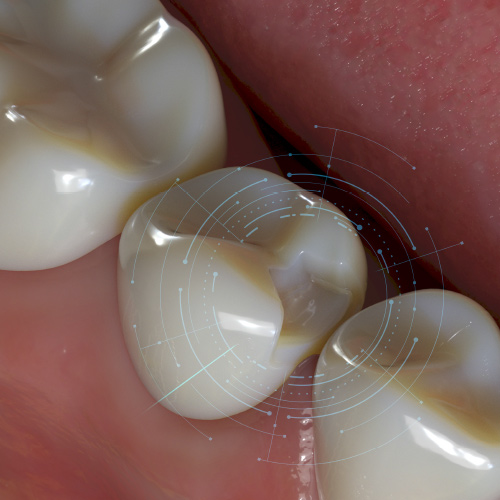

Leveraging AI for Diagnostic Excellence

Wednesday, June 5, 2024

The newest advancements in diagnostic imaging incorporate assisted intelligence (AI). Software can now help dentists more precisely and accurately identify areas of concern, trace the mandibular nerve, accurately plan dental implants, organize all images into a single template, and much more.